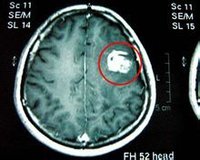

裂頭蚴可侵入皮下組織形成皮下結節,也可侵犯腹腔內臟器、組織,還可穿過橫隔侵犯胸腔,危害最大的是侵入眼部和大腦中樞神經系統,形成蜂窩狀囊腔而導致嚴重後果,可致殘疾和危及生命。

近年來,媒體經常報導有人因吃青蛙導致裂頭蚴進入大腦的事件,最後都是通過開顱手術將蟲體摘除,稍有不慎,便可能致殘致死,風險極大。吃青蛙一般感染1~4條,但喝蛇血感染數量巨大,一般達上百條。